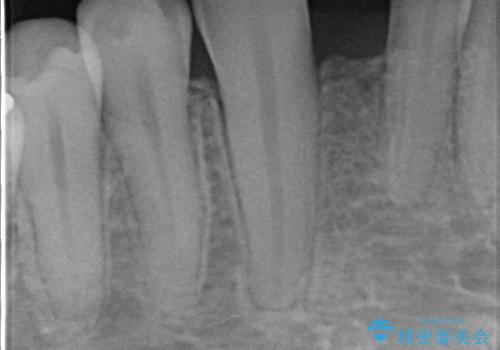

ブリッジにすることも可能でしたが、両側の歯が天然歯であること、また、事前に矯正で噛み合わせを整え、幅も確保していたこと、CTにより骨の厚みがある程度あったことを踏まえ、インプラントも可能であるとお話しし、選んでいただきました。

唇側の骨増成もしっかり行い、前歯部インプラントによくある、歯茎が下がって見えることもない、審美的なインプラント補綴ができました。